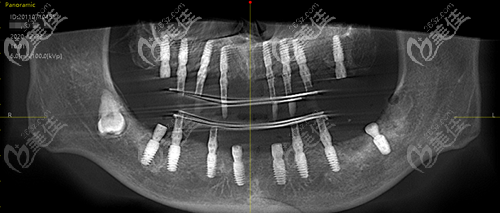

来看看泉州维乐高难度全口牙齿种植效果吧!

ct对比

老人牙齿ct情况